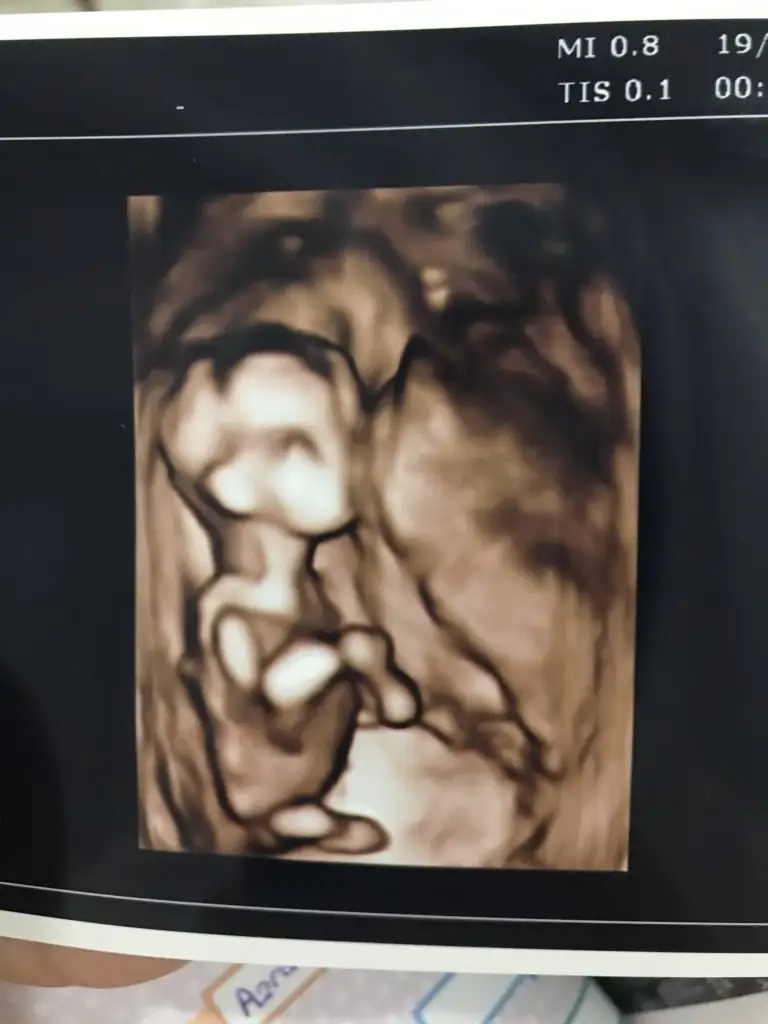

Bunlar net değilBi de bu resimler var.

Kaç haftalık usg sanki erkek gibi eminde olmadım 11 12 13 haft usgler olmalı tekrar usg paylaşınMerhabalar tahmininizi çok merak ediyorum :)

Üçlü taramada büyük ihtimalle kız olduğu söylendiNet degil usg tek tek çekermisiniz usgler yada başka usg olursa paylaşın 12-13 haftalarda olabilir şimdilik eminde değilim kız gibi gibi emin değilim tekrar usg paylaşın